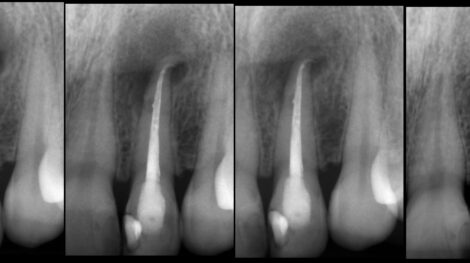

Leczenie zmiany zapalnej